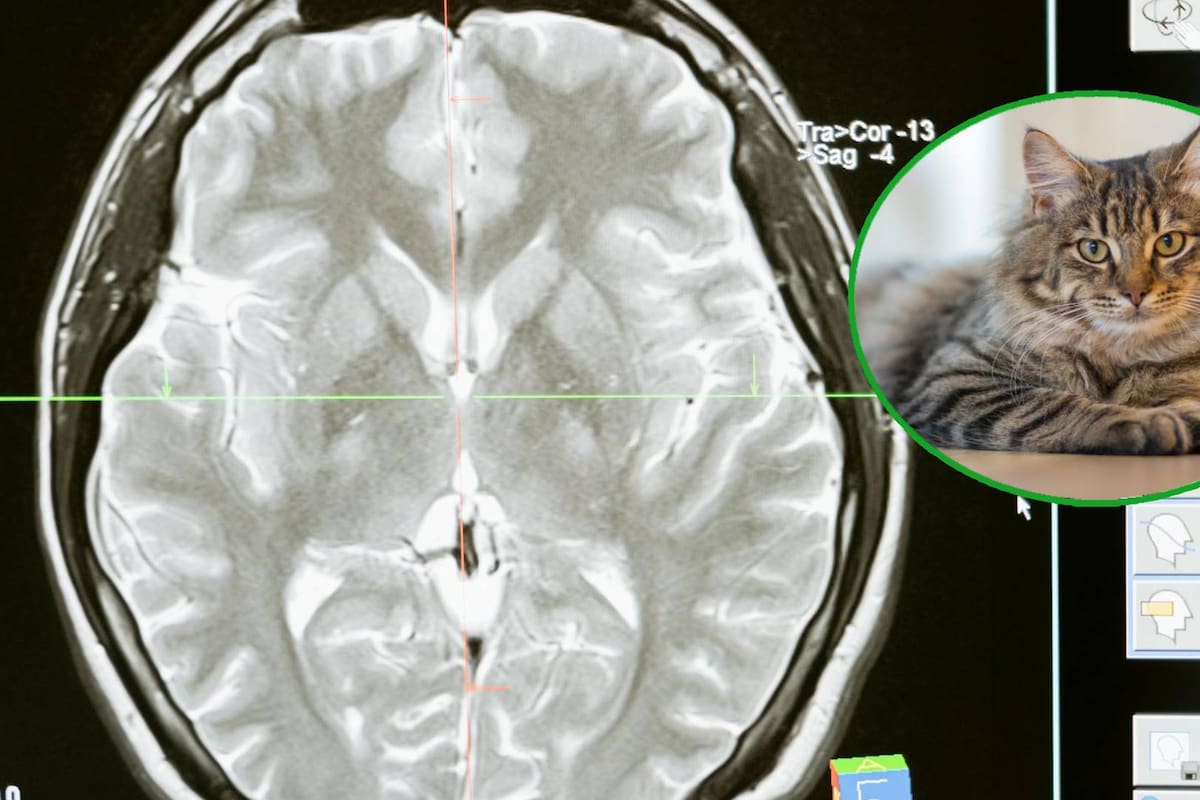

ISRAEL.- Investigadores de la Universidad de Tel Aviv en Israel, liderados por el profesor Oded Rechavi, han encontrado que el Toxoplasma gondii puede ser manipulado con la finalidad de atravesar la barrera hematoencefálica y entregar proteínas directamente a las neuronas en el cerebro.

Se ha demostrado que tiene la capacidad de viajar desde el sistema digestivo hasta el cerebro y secretar proteínas en células cerebrales. La barrera hematoencefálica protege al cerebro de agentes externos, dificulta también la entrada de tratamientos.

De acuerdo a la nota publicada en The Sun, la capacidad del Toxoplasma gondii para cruzar esta barrera, podría facilitar el desarrollo de nuevas terapias para enfermedades neurológicas. Este parásito se puede encontrar en las heces de los gatos

Este avance podría tener aplicaciones significativas en el tratamiento de enfermedades neurológicas como el Alzheimer y el Parkinson.

El equipo de investigación, en colaboración con la Universidad de Glasgow en Escocia, ha trabajado en diseñar el Toxoplasma gondii y pudiera transportar la proteína MeCP2, una molécula de interés para tratar el síndrome de Rett. En modelos de ratones, los parásitos produjeron y entregaron exitosamente la proteína a células cerebrales.

El trabajo publicado en la revista Nature Microbiology destaca el avance en la utilización de parásitos para la administración de medicamentos.

La profesora Lilach Sheiner de la Universidad de Glasgow, enfatizó que se requerirán años adicionales de investigación y desarrollo para convertir estos hallazgos en tratamientos viables y seguros para los pacientes.